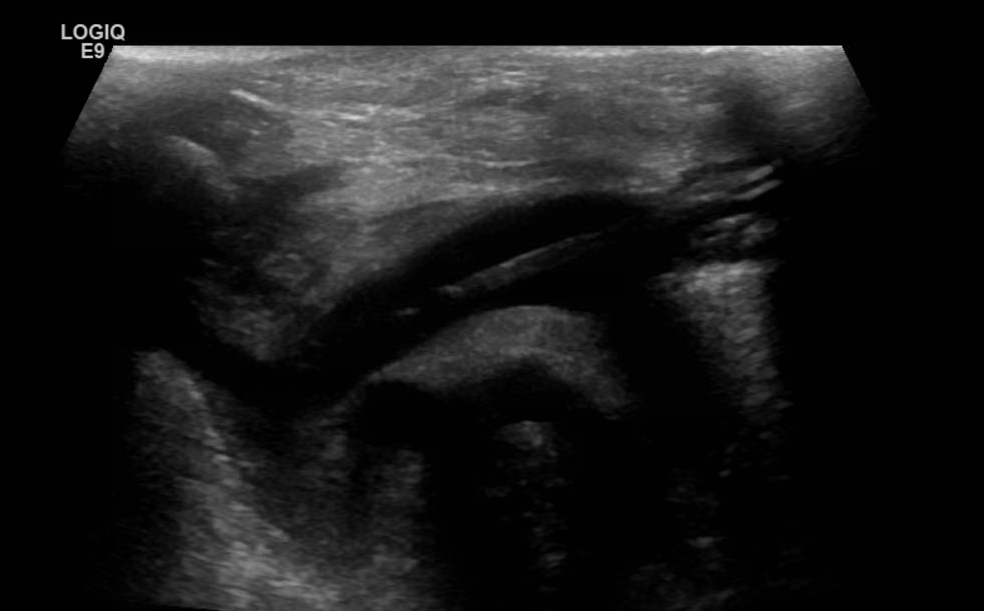

Thrombosis of the right innominate vessel with indwelling catheter